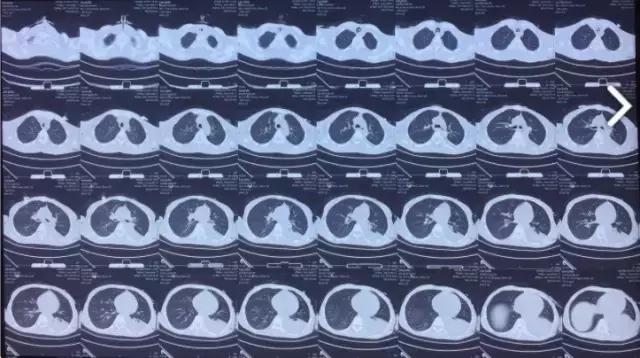

菅老师您好,非常抱歉,我们医院的核磁共振坏了几天了,复查的头部CT 未见明显异常,胸部CT 可见左侧胸腔积液明显,具体见下图,脑电图没有做,之后等修好了磁共振再给您结果,我想问,我们医院没有维生素B1注射剂,家属出去外购,这个药物只能肌肉注射,我要问的是,如果给予稀释后静脉滴注怎么样呢,通过肌注几支后,我感觉,症状有所好转,精神状态明显好转,只是抽搐还继续存在。

(部分CT图片)

情况已经了解具体意见如下供参考:.1肌肉注射的药物不能静脉注射。肺部改变,和我们当初分析的完全一致。颅脑核磁共振,还应该想办法做。做完了,以后我们应该能有所发现。保持联系,供参考。